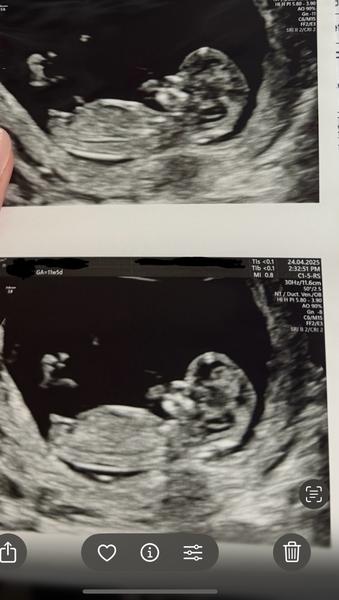

Může někdo určit pohlaví podle ultrazvuku ve 13+3 týdnu?

@hollynka těžko říct, jestli to co je vidět je pohlavní hrbolek, tak je to holčička. Já si podle něj sama určila tenkrát dceru 😁teď jsem to věděla z NIPT. Jsou lékaři, co se trefí už ve 13 tt, co to umí. A pak jsou i lékaři, kteří i kolem 20 tt vahaji.

Mě přijde, ze holka.

@ovesova taky bych řekla, ze holka... vypadá to stejně jako z naseho UZ ve 14tt 😃

@hollynka myslim si, ze holka 🤗